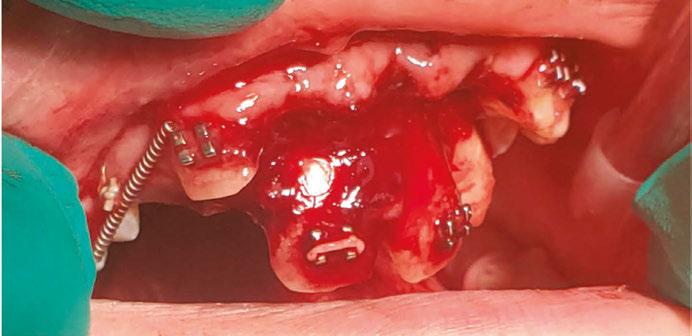

Luckily, the young boy was undergoing orthodontic treatment so the avulsed teeth remained in the oral cavity. As you can see from the clinical photograph in Figure 1, teeth Nos. 8, 9, and 10 would not have remained in the mouth if the orthodontic wire was not in place.

Figure 1